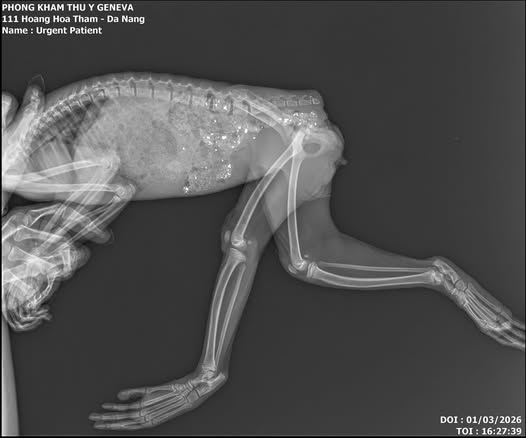

Kết quả chụp X-quang cho thấy phần đuôi của khỉ đã bị cắt cụt với vết cắt sát đốt xương. "Tháo đuôi khỉ" là hình thức can thiệp thô bạo, thường xảy ra ở các cá thể bị nuôi làm thú cưng để dễ dàng hơn cho việc mặc quần áo như con người, khiến chúng trông "dễ thương" hơn.

Kết quả X-quang của chú khỉ vàng

Ảnh: Ngọc Trúc

Chị Ngọc Trúc chia sẻ: "Hiện tại khỉ được chữa trị tại bệnh viện thú y Geneva Đà Nẵng. Tình trạng 2 chi sau bị liệt và khả năng đi lại được rất thấp. Phần chai mông bắt đầu lở loét do ngồi nhiều và đi tiểu không tự chủ. Các bác sĩ nhận định con khỉ này không thể tái thả về tự nhiên khi 2 chi sau bị liệt và không có khả năng kiếm ăn trong tự nhiên".